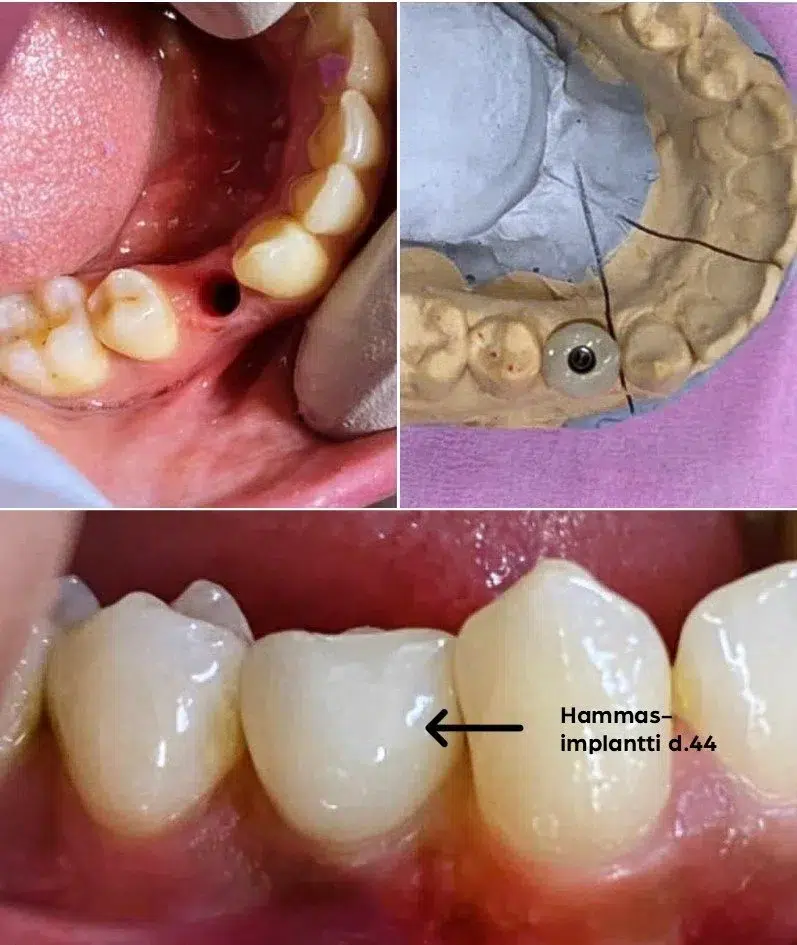

Immediaatti-implantointi lyhentää implanttihoidon kestoa, vähentää kirurgisten toimenpiteiden määrää ja parantaa estetiikkaa. Välittömässä implanttihoidossa keinojuuri ja väliaikainen hammaskruunu asetetaan hampaan poistokuoppaan heti hampaan poiston jälkeen, yhden vastaanottokäynnin aikana.

Ensimmäisen hoitokerran jälkeen implanttiruuville annetaan muutaman kuukauden mittainen luutumisaika, jonka jälkeen implanttiin päästään kiinnittämään pysyvä, useimmiten keraaminen hammaskruunu. Luutumisaika on yhtä pitkä kuin perinteisessä implanttihoidossa.

Kun implantointi tehdään immediaattina, hoito on tavanomaista nopeampi ja tuloksetkin usein tavallista esteettisempiä.